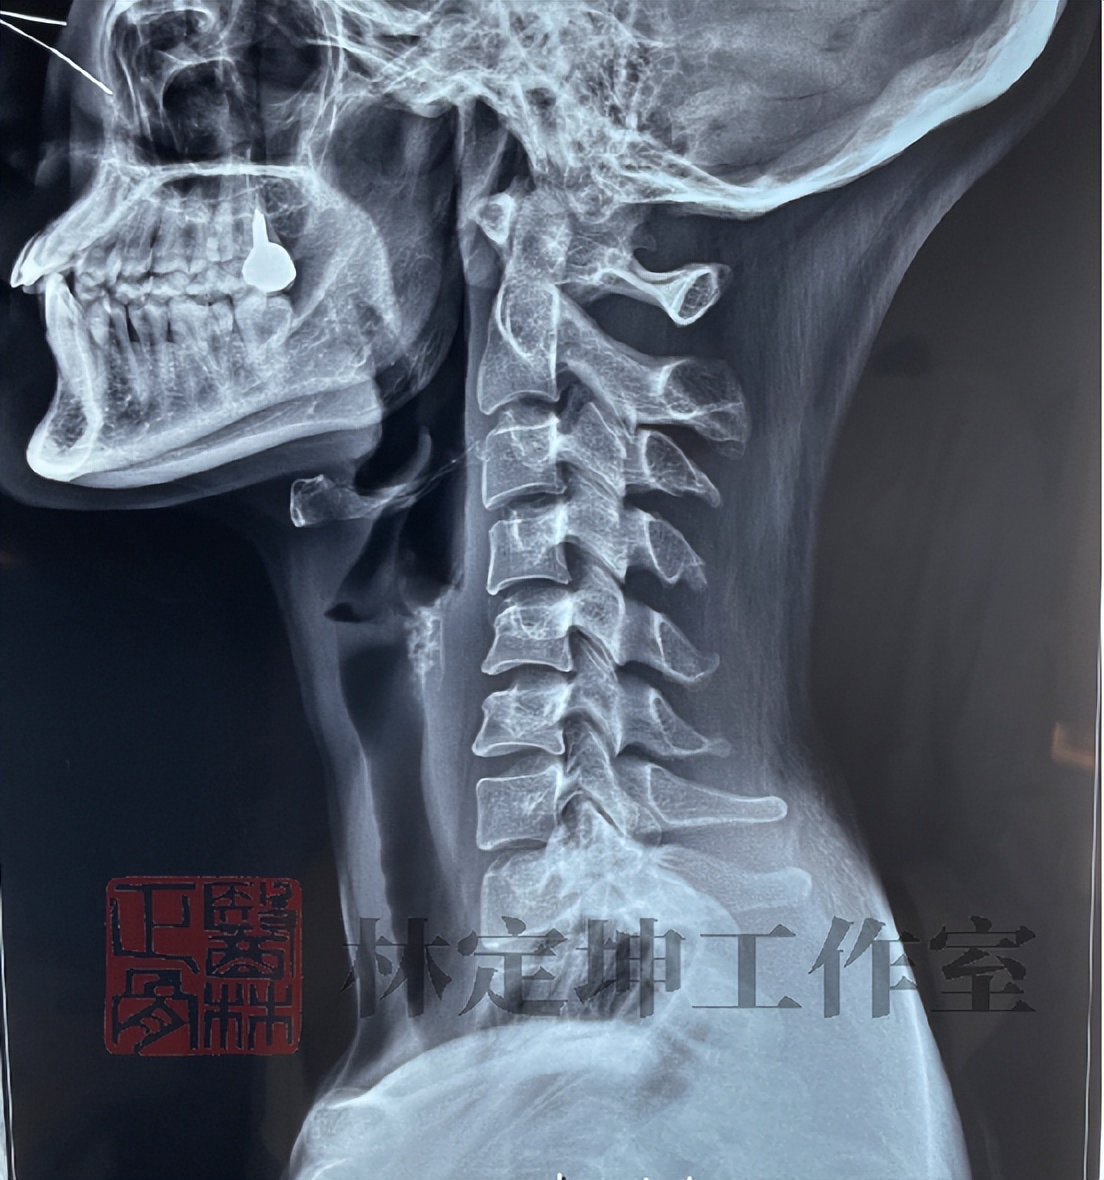

三、生理曲度变直

在做完颈椎X线片检查后,“生理曲度变直”成为了压在不少人心上的大石头。

“脖子已经 没有曲度,很严重 !”、“如果不及时治疗,发展成更严重的颈椎病,就来不及了!”这些环绕在身边的传闻,让很多人产生了许多焦虑的情绪,不仅试了很多网传方法,还来来回回跑好几趟医院。

单纯的生理曲度变直并不是病,而是一种颈椎在长时间的不良应力下产生的 一种状态 ,并不可怕。

1、无明显不适,重养护

在没有其他不适,或者只是偶尔有颈部酸痛不影响正常生活的情况下,不必太过关注,只需做好 日常颈椎养护的四方面 即可(点击链接可跳转查看:医林正骨丨居家护养四大措施)。

2、有症状,进一步诊查

而如果出现了明显的颈痛、手臂痛等症状,则建议在做好养护的基础上及时就医,做进一步的检查和治疗。